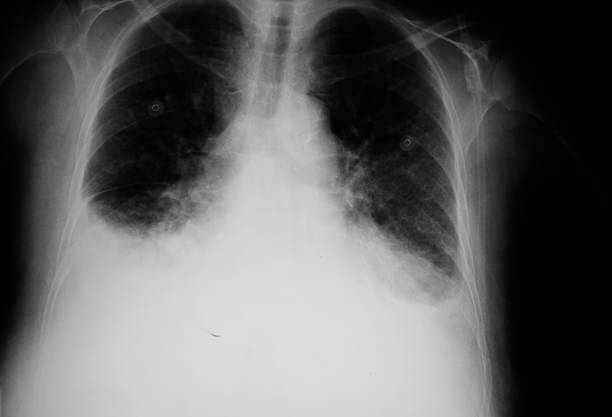

합병증 확인: 폐부종과 관련된 합병증 여부를 확인하기 위해 흉부 X-선, CT 스캔, 혈액검사 등이 수행될 수 있습니다. 이는 폐 이외의 다른 기관과 조직의 상태를 확인하는데 도움을 줍니다.